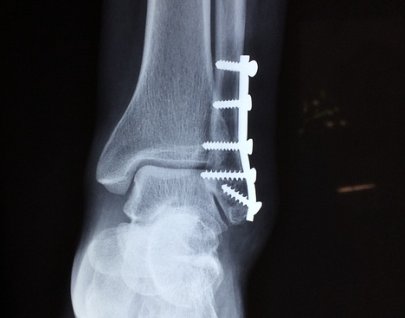

4) 골절 및 골관절염

발목 뼈의 골절이나 관절염도 통증을 유발하는 주요 원인 중 하나입니다. 골절의 경우 외부 충격으로 인해 발생하며, 심한 경우 수술적 치료가 필요할 수도 있습니다. 골관절염은 노화로 인해 연골이 닳으면서 발생하며, 만성적인 발목 통증과 부종을 동반할 수 있습니다.

치료방법:

- 골절의 경우 X-ray 촬영 후 깁스나 수술적 치료를 진행합니다.